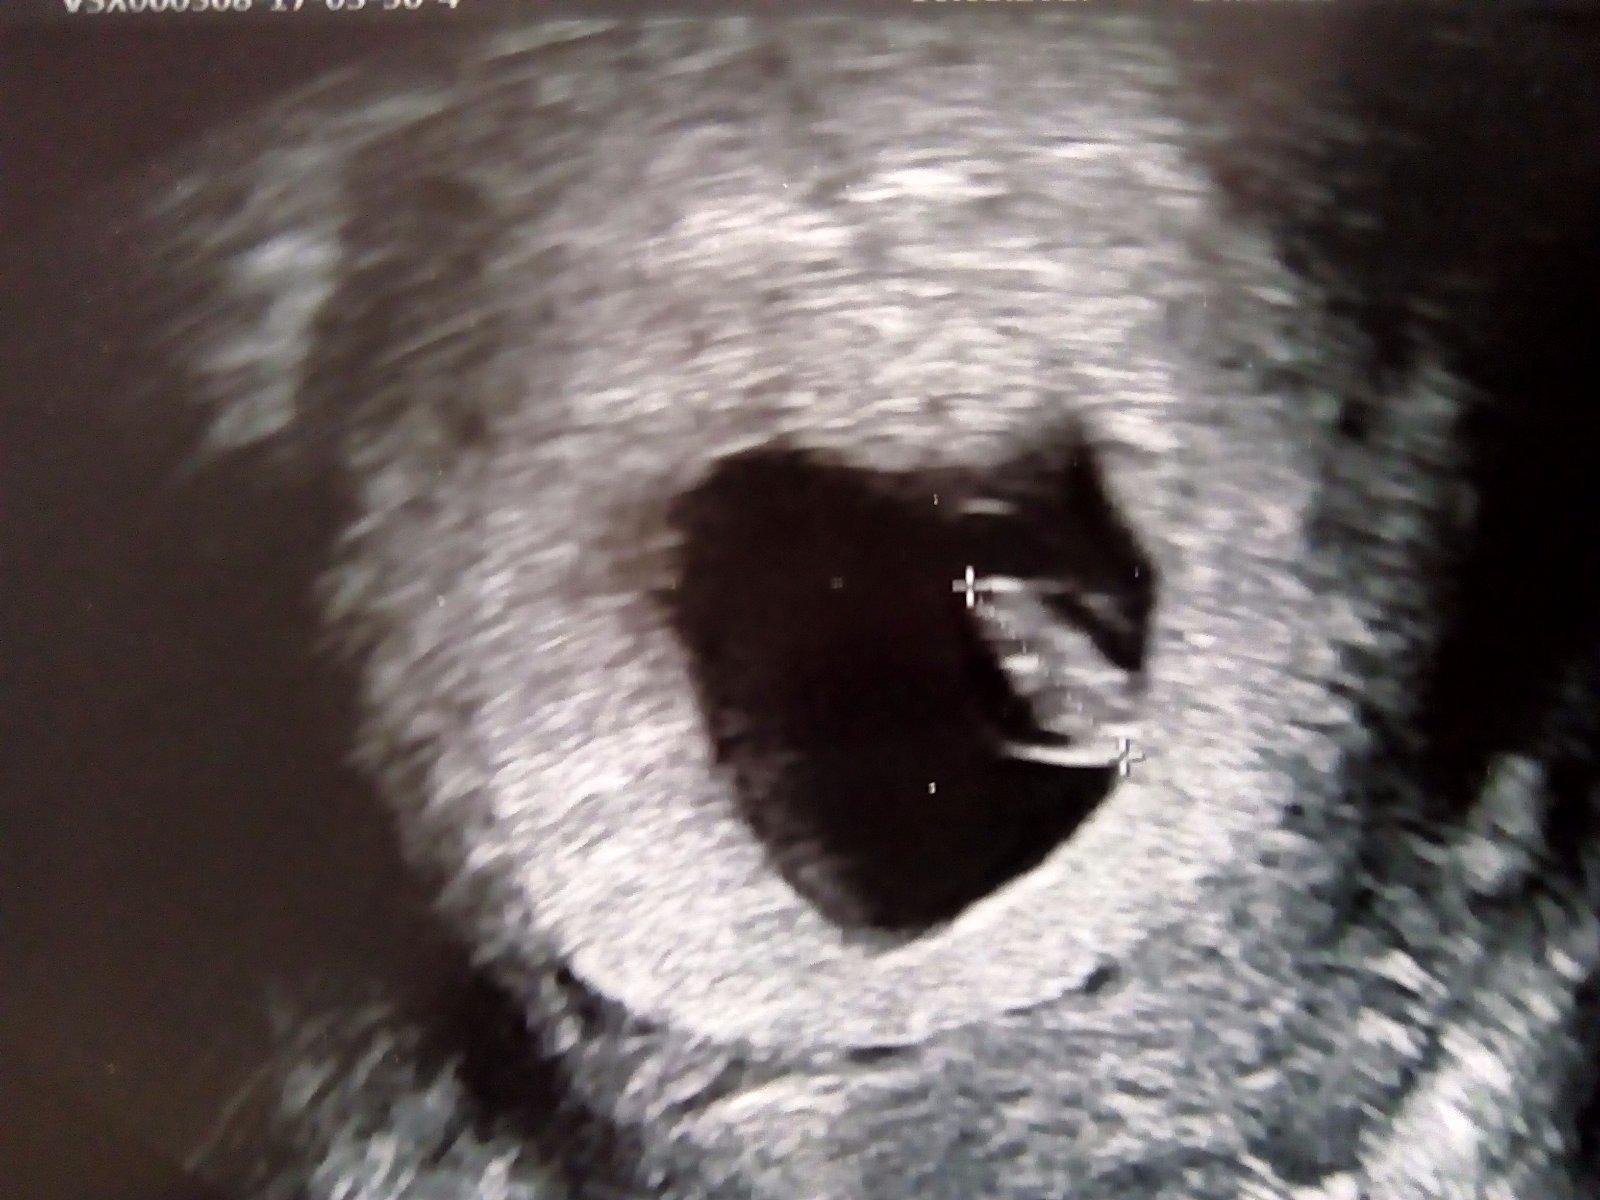

Ovulační test, je pozitivní?

Holky, poradte je nebo neni 🙂?